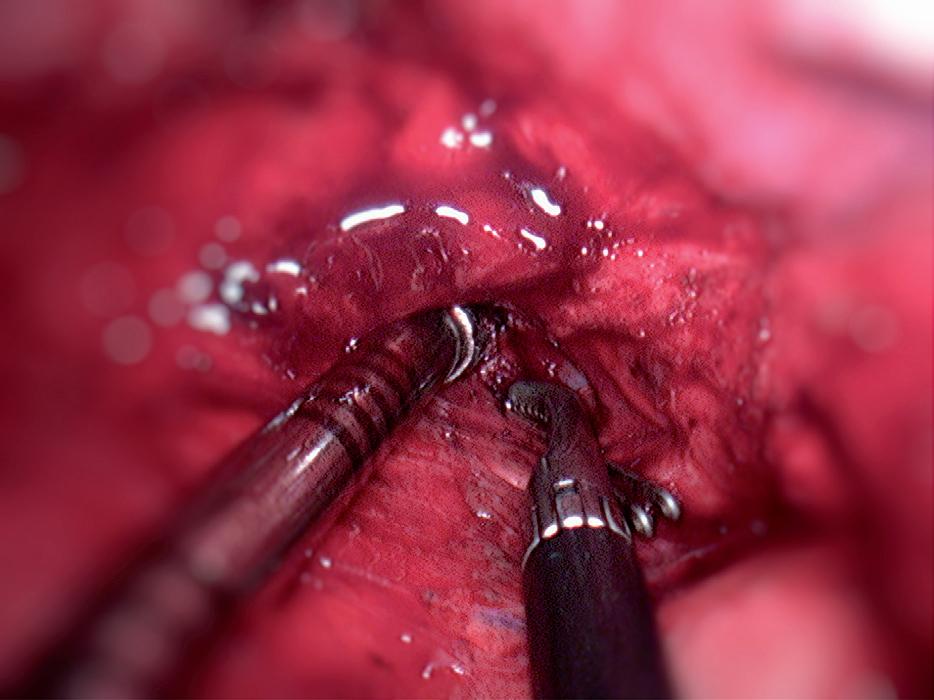

6.4.3 nástroje k videotorakoskopické operativě

Nástroje k videotorakoskopii lze rozdělit různými způ soby. Pro přehlednost je můžeme dělit na klasické la paroskopické a specializované, upravené pro specifické potřeby videotorakoskopií, včetně potřeb uniportálního přístupu. K torakoskopickým výkonům ale s úspěchem využijeme i některé nástroje určené primárně pro ote vřenou operativu. a b

obr. 6.14 Disektor používaný běžně v laparoskopii se dobře hodí i v pokročilé videotorakoskopii zejména pro preparaci v úzkých prostorech v přímém směru. Na obrázku spolu s preparační savkou (a). Stejně tak rovné laparoskopické nůžky jsou efektivně použitelné v torakopskopii pro přerušení tkání střihem, koagulací nebo, přirozeně, jejich kombinací (b). Protože s nimi lze i disekovat, mají univerzálnější použití než tradiční videoskopický koagulační háček